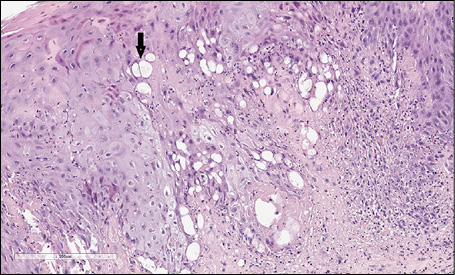

At scanning magnification, the histopathology showed a broad dermo-epidermal ulceration with an underlying purulent base (Figure 2). At higher magnification, the epidermis was characterized by necrotic keratinocytes with pycnotic nuclei and dense eosinophilic cytoplasm (Figure 3, arrowhead) and by scattered keratinocytes with a “shadow cell” appearance (enlarged cells with eosinophilic cytoplasm without well-defined nuclei [Figure 3, arrow]); suppurative changes were detected within the papillary dermis with marked neutrophilic exocytosis (Figure 3, asterisk). Some keratinocytes showed ballooning degeneration (Figure 4, arrow). An interstitial and perivascular/peri-adnexal inflammatory infiltrate composed of neutrophils and lymphocytes was observed in the deep dermis, associated with endothelial swelling (Figure 5, arrowhead) without fibrinoid necrosis of the vascular wall.

Figure 4 - Haematoxylin and eosin (H&E) stain. The keratinocytes showed ballooning degeneration (arrow): keratinocytes appear swollen, pale, and round due to intra-cellular oedema and loss of intercellular bridges (magnification 40x).